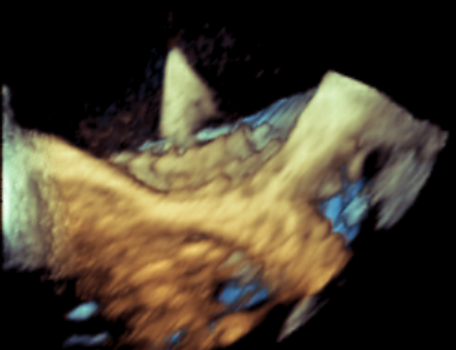

术中影像监护与评估(DSA&TEE)

CDFI提示过瓣血流通畅

CDFI示少量瓣周漏

收缩期未见瓣周漏